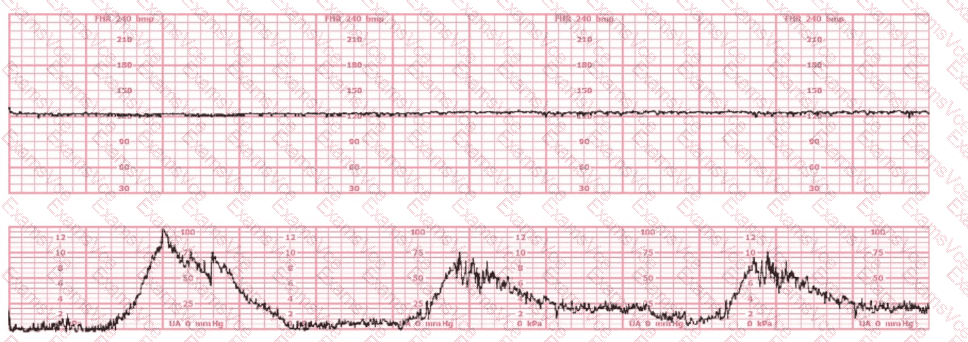

The fetal heart rate tracing shows:

This pattern is Category II, but in the context of:

28-week gestation

Immediate postoperative status after anesthesia

Maternal alertness and stability

NCC and AWHONN emphasize that maternal sedation, post-anesthesia effects, medications, and physiologic stress commonly cause temporary minimal variability without acidemia, especially at preterm gestations where baseline variability is normally lower.

Minimal variability in a stable mother without decelerations does NOT require emergent delivery.

Instead, the fetus should be observed as anesthesia effects wear off.